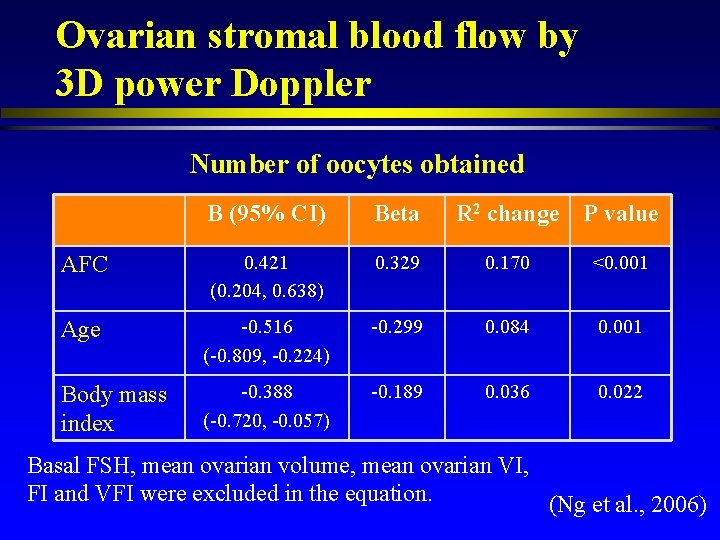

Ovarian stromal blood flow by 3 D power Doppler Number of oocytes obtained B (95% CI) Beta R 2 change P value AFC 0. 421 (0. 204, 0. 638) 0. 329 0. 170 <0. 001 Age -0. 516 (-0. 809, -0. 224) -0. 299 0. 084 0. 001 Body mass index -0. 388 (-0. 720, -0. 057) -0. 189 0. 036 0. 022 Basal FSH, mean ovarian volume, mean ovarian VI, FI and VFI were excluded in the equation. (Ng et al. , 2006)